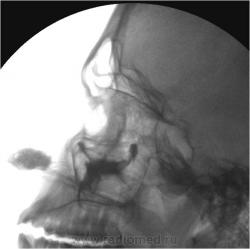

С гайморографией "сталкивался" весьма редко.

Это по всей видимости, кистозные образования?

Да - это кисты.